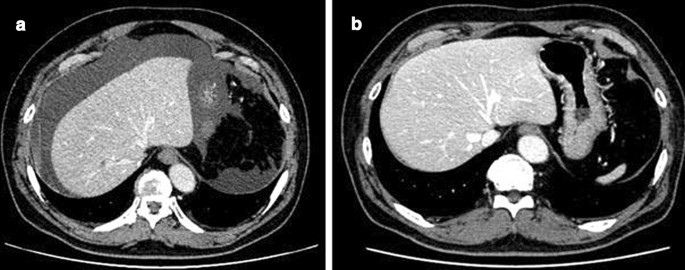

A 62-year-old man presented to a nearby clinic with a chief complaint of abdominal fullness and abdominal pain. His medical history was not significant. He was on no medication. He was not allergic to any drug or food. Laboratory tests showed increased peripheral white blood cell count (17,900/µL) and eosinophil count (12,100/µL), measured by an automated hematology analyzer, Sysmex XN 2000 (Sysmex corporation, Hyogo, Japan). Abdominal computed tomography (CT) showed massive ascites and no other abnormalities (Fig. 1a).

After administration of systemic steroid therapy (prednisolone (PSL) 60 mg/day, 1 mg/kg/day), his blood eosinophil count and weight decreased immediately. The dose of PSL was then decreased biweekly. One and a half months after steroid administration, abdominal CT confirmed disappearance of ascites (Fig. 1b). Laparoscopic left hemicolectomy with regional lymph node dissection (D3) was performed. At laparoscopy, the inflammation of the mesentery and omentum was seen to be relieved, and there was no ascites (Fig. 2b, d). The patient’s postoperative course was uneventful, and he was discharged on the 5th postoperative day. According to the Union for International Cancer Control TNM classification 8th Edition, the pathological diagnosis was tubular adenocarcinoma, moderately differentiated, pT3 (SS), int, ly1, v1, PN1, EX0, pN0, sM0, pStage IIA. The pathological specimen also showed eosinophilic infiltration to various lesions, especially omentum, mesentery, and the submucosal layer of the descending colon. He was given adjuvant oral chemotherapy (uracil-tegafur with leucovorin) for six months because there was concern that the pathological ly1 and v1 could increase the risk for recurrence of the cancer [7].